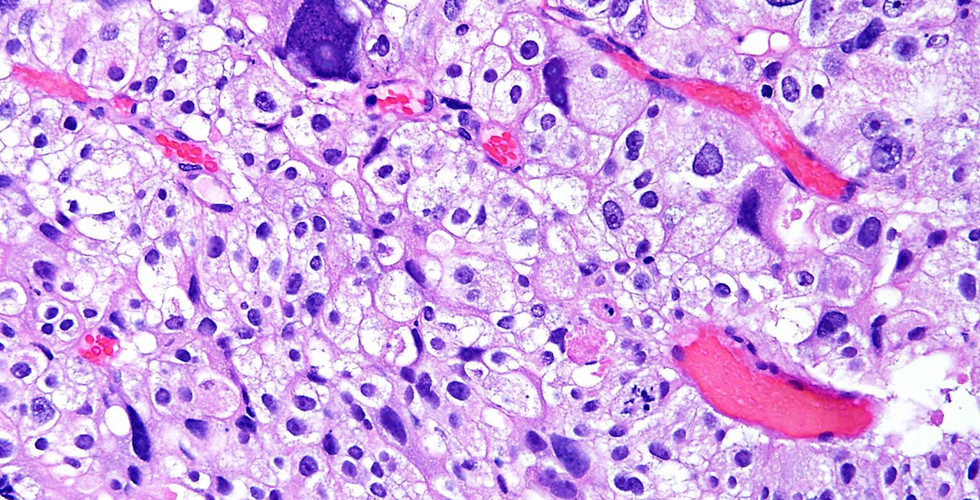

Prostatic carcinoma with pleomorphic giant cells is a rare and aggressive variant of prostate adenocarcinoma characterized by large pleomorphic cells with bizarre nuclear atypia. In needle biopsies, the pleomorphic giant cell component is usually focal and the associated adenocarcinoma is high-grade (Gleason score 9 or 10, Grade Group 5). Most patients whose samples show this finding have not had prior irradiation. The main differential diagnosis is with urothelial carcinoma with giant cells, which is a more common and better recognized entity. This beautiful image and discussion were provided by Dr. Andres Matoso. His book, Survival Guide to Prostate Pathology, created together with Dr. Jonathan Epstein, is wonderful - an easy to use "'scope-side" resource. Get yours at www.innovativesciencepress.com